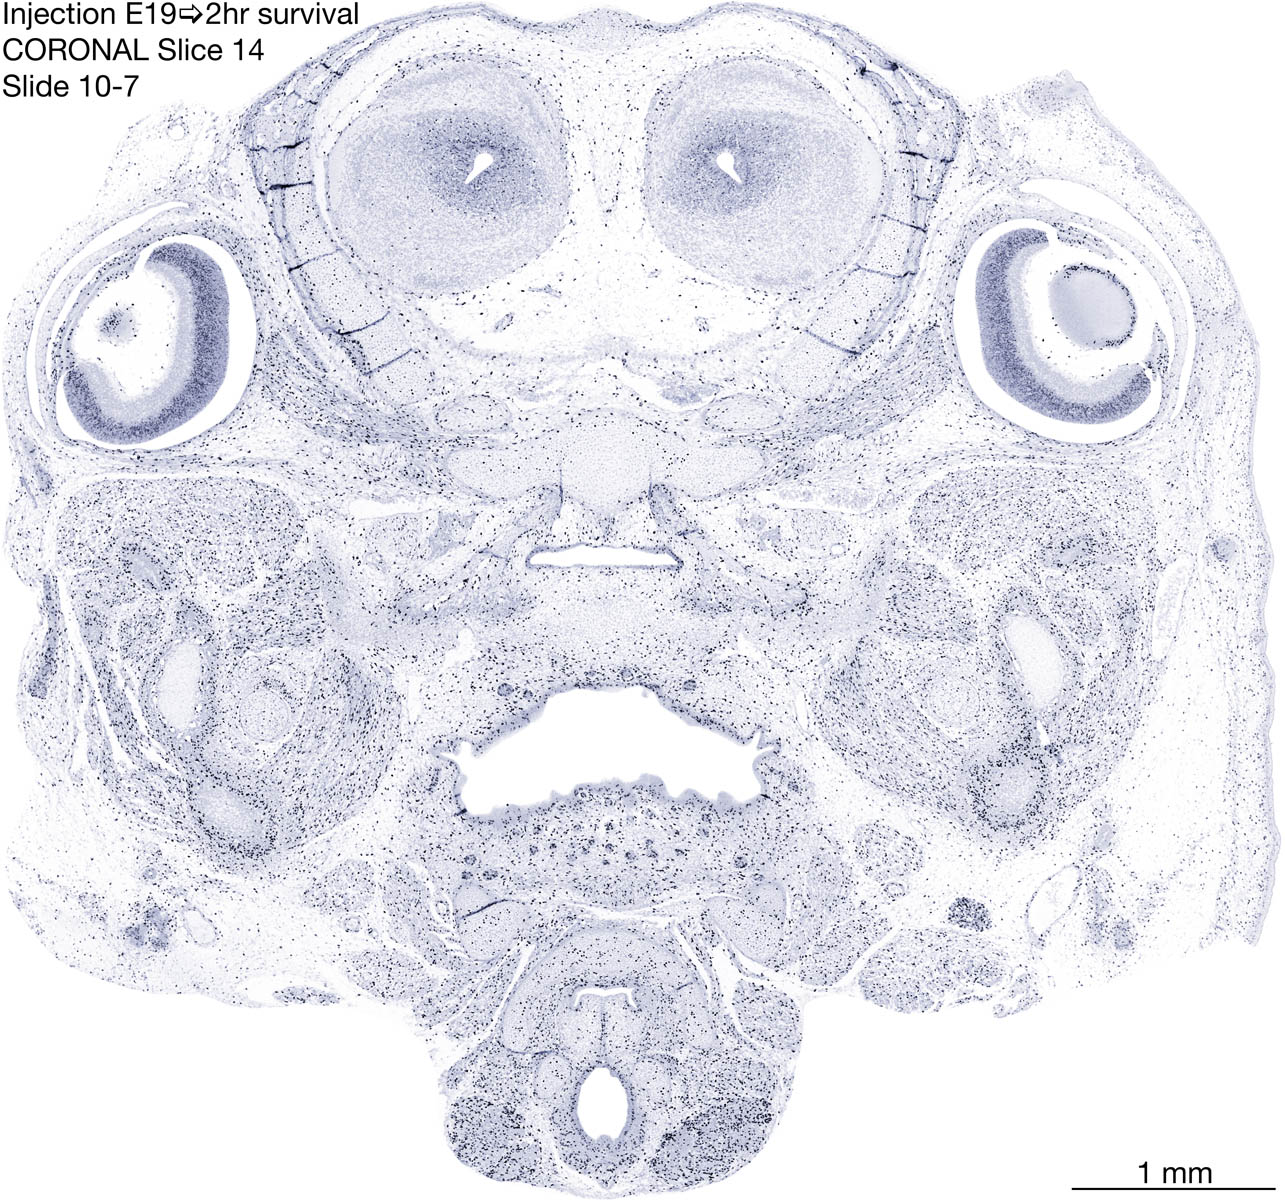

E19 2hr Survival Archived Images-Coronal The following images are from a paraffin-embedded coronally-sectioned head of an E19 rat embryo exposed to tritiated thymidine 2 hours before death. Download: Large | High Res Download: Large | High Res Download: Large | High Res Download: Large | High Res Download: Large | High Res Download: Large | High Res Download: Large | High Res Download: Large | High Res Download: Large | High Res Download: Large | High Res Download: Large | High Res Download: Large | High Res Download: Large | High Res Download: Large | High Res Download: Large | High Res Download: Large | High Res Download: Large | High Res Download: Large | High Res Download: Large | High Res Download: Large | High Res Download: Large | High Res Download: Large | High Res Download: Large | High Res Download: Large | High Res Download: Large | High Res Download: Large | High Res Download: Large | High Res Download: Large | High Res Download: Large | High Res Download: Large | High Res Download: Large | High Res Download: Large | High Res Download: Large | High Res Download: Large | High Res Download: Large | High Res Download: Large | High Res Download: Large | High Res Download: Large | High Res Download: Large | High Res Download: Large | High Res Download: Large | High Res Download: Large | High Res Download: Large | High Res Download: Large | High Res Download: Large | High Res Download: Large | High Res Download: Large | High Res Download: Large | High Res Download: Large | High Res Download: Large | High Res Download: Large | High Res Download: Large | High Res Download: Large | High Res Download: Large | High Res Download: Large | High Res Download: Large | High Res Download: Large | High Res Download: Large | High Res Download: Large | High Res Download: Large | High Res Download: Large | High Res Download: Large | High Res Download: Large | High Res Download: Large | High Res Download: Large | High Res Download: Large | High Res Download: Large | High Res Download: Large | High Res Download: Large | High Res Download: Large | High Res Download: Large | High Res Download: Large | High Res Download: Large | High Res Download: Large | High Res Download: Large | High Res Download: Large | High Res Download: Large | High Res Download: Large | High Res Download: Large | High Res Download: Large | High Res Download: Large | High Res Download: Large | High Res Download: Large | High Res Download: Large | High Res Download: Large | High Res Download: Large | High Res Download: Large | High Res Download: Large | High Res Download: Large | High Res Download: Large | High Res